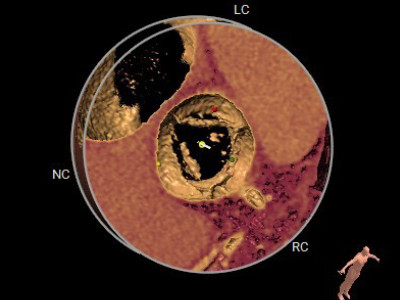

患者术前CT分析:患者主动脉瓣为三叶式,瓣叶重度钙化伴增厚;左侧冠脉开口9.1mm稍低;主动脉弓角度偏小。

瓣环

开口面积

左冠高度

钙化积分

外周血管通道